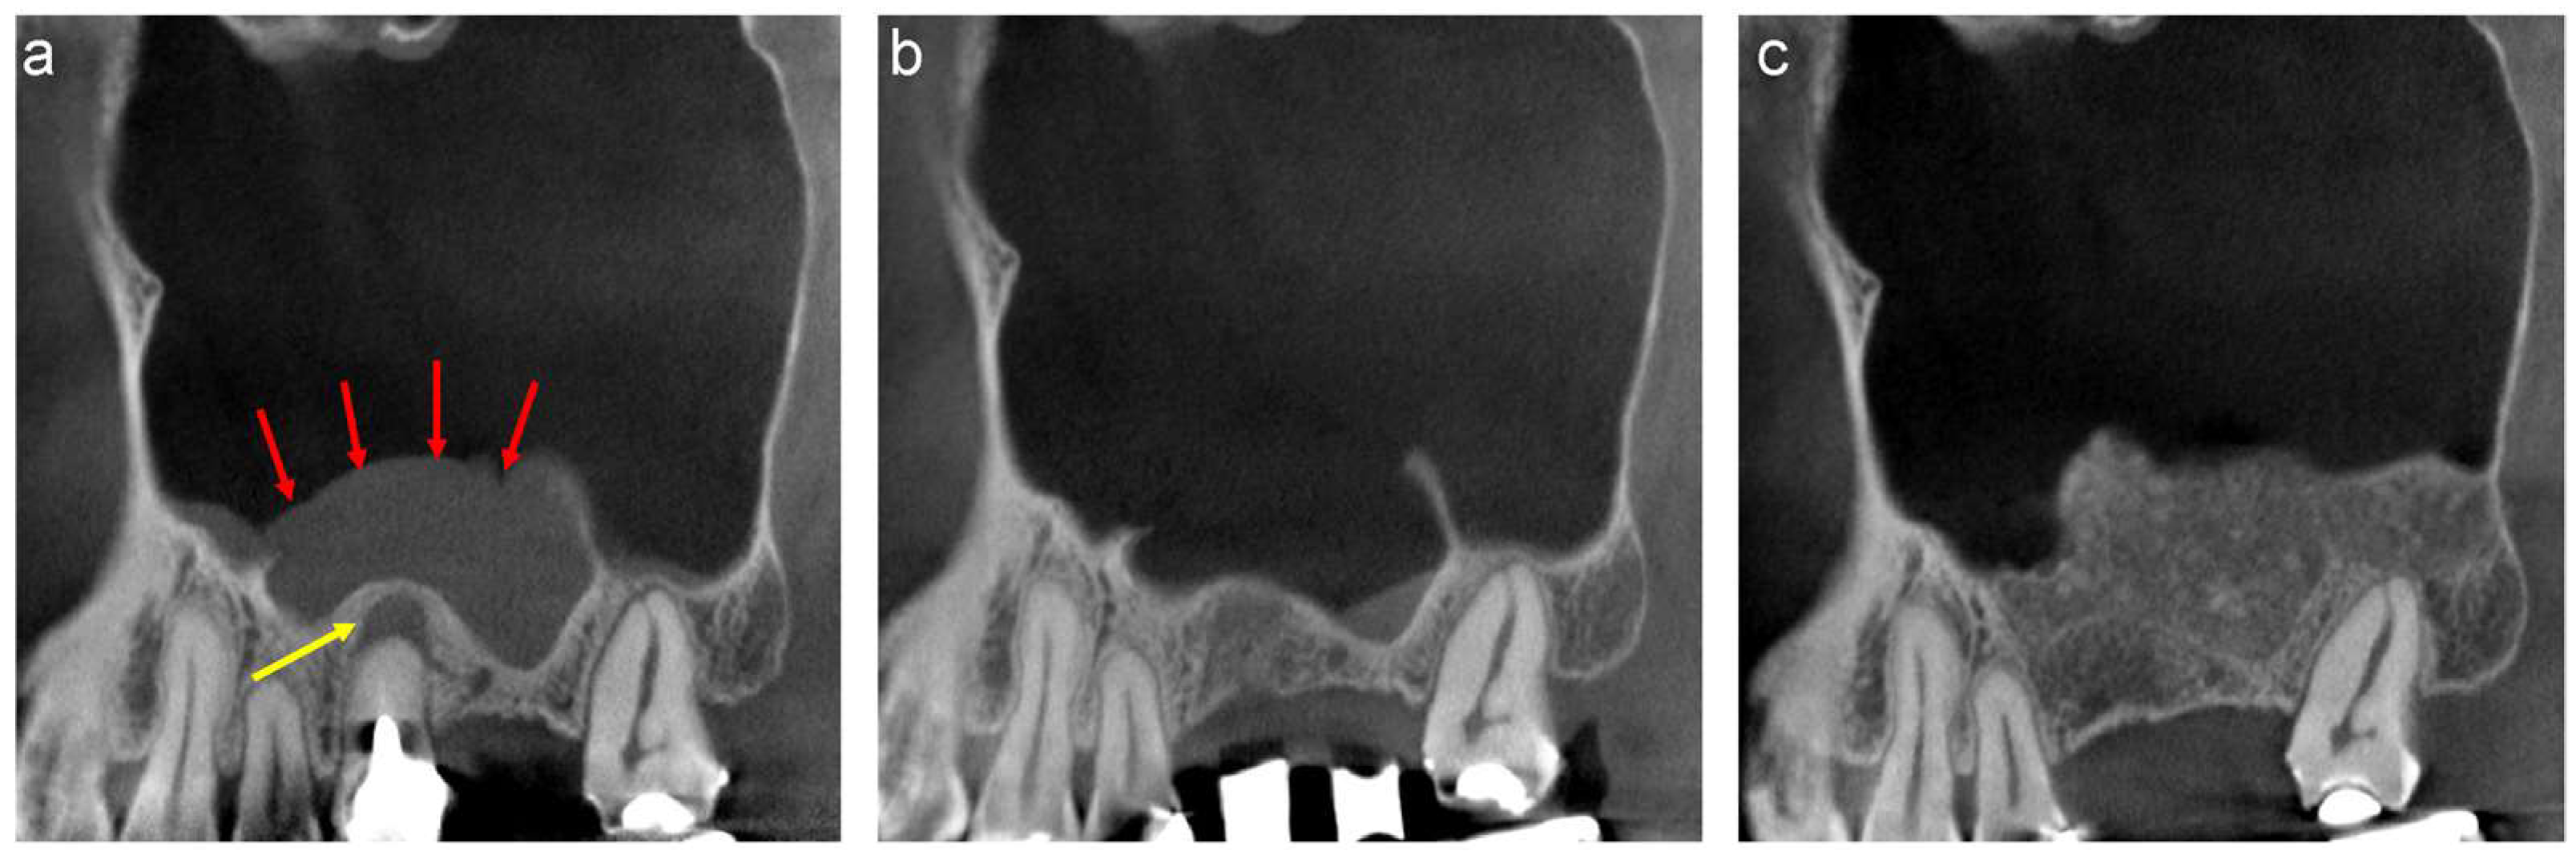

A 44-year-old female scheduled to undergo implant placement for the replacement of 27 was referred to our clinic in 2014 for sinus floor elevation owing to insufficient bone height. A well-defined, faintly radiopaque antral lesion was observed on the mesiodistal section of the CT image acquired at the first visit (Figure 2a, red arrows). A periapical lesion was observed at the palatal root apex of 26, indicating periapical disease (Figure 2a, yellow arrow); consequently, the tooth was extracted by the original dentist. The antral radiopaque lesion had disappeared almost completely four months after the extraction (Figure 2b). Thus, sinus floor elevation was performed using β-TCP granules alone at our clinic. CT image acquired nine months postoperatively revealed a radiopaque area at the site where sinus floor elevation was performed without swelling of the sinus membrane (Figure 2c).

Figure 2.

The mesiodistal section of CT images of the left maxillary sinus. (a) Well-defined, faintly radiopaque antral lesions (red arrows) and bone resorption at the palatal root apex of 26 (yellow arrow) are observed. (b) Almost all well-defined, faintly radiopaque antral lesions had disappeared four months after the extraction. (c) A radiopaque area is observed at the sinus floor elevation without swelling of the sinus membrane nine months postoperatively.